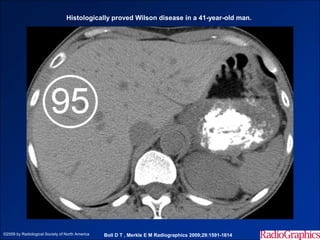

Histologically proved Wilson disease in a 41-year-old man.

©2009 by Radiological Society of North America   Boll D T , Merkle E M Radiographics 2009;29:1591-1614

Histologically proved Wilsondisease in a 41-year-old man. ©2009 by Radiological Society of North America Boll D T , Merkle E M Radiographics 2009;29:1591-1614

• #20 Histologically proved Wilson disease in a 41-year-old man. Nonenhanced image from multidetector CT shows increased attenuation of the hepatic parenchyma. Circle = region of interest, number = attenuation in Hounsfield units.